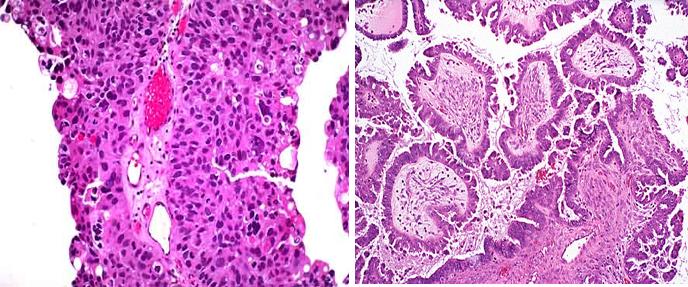

(1)良性: |

|

(2)恶性: |